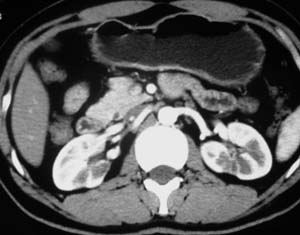

以下是引用子期在2010-3-19 20:47:00的发言:[br]血管畸形的ct增强应该有明显强化,本例并不相符合。本例双肾局部的略低密度影,累及肾盂,局部皮质明显变薄、内陷,增强扫描有轻度的强化,应考虑为炎性病变,患者为年轻男性,累及双肾的感染以结核较常见,可以没有明显的临床症状,尿中有时候也并不能查出什么;肾脓肿常有明显感染中毒症状,本例不符,另外一般的肾盂肾炎或肾小球肾炎通过小便就可确诊,其它还不能排除的是黄色肉芽肿性肾盂肾炎,然而单凭ct一般也很难鉴别。